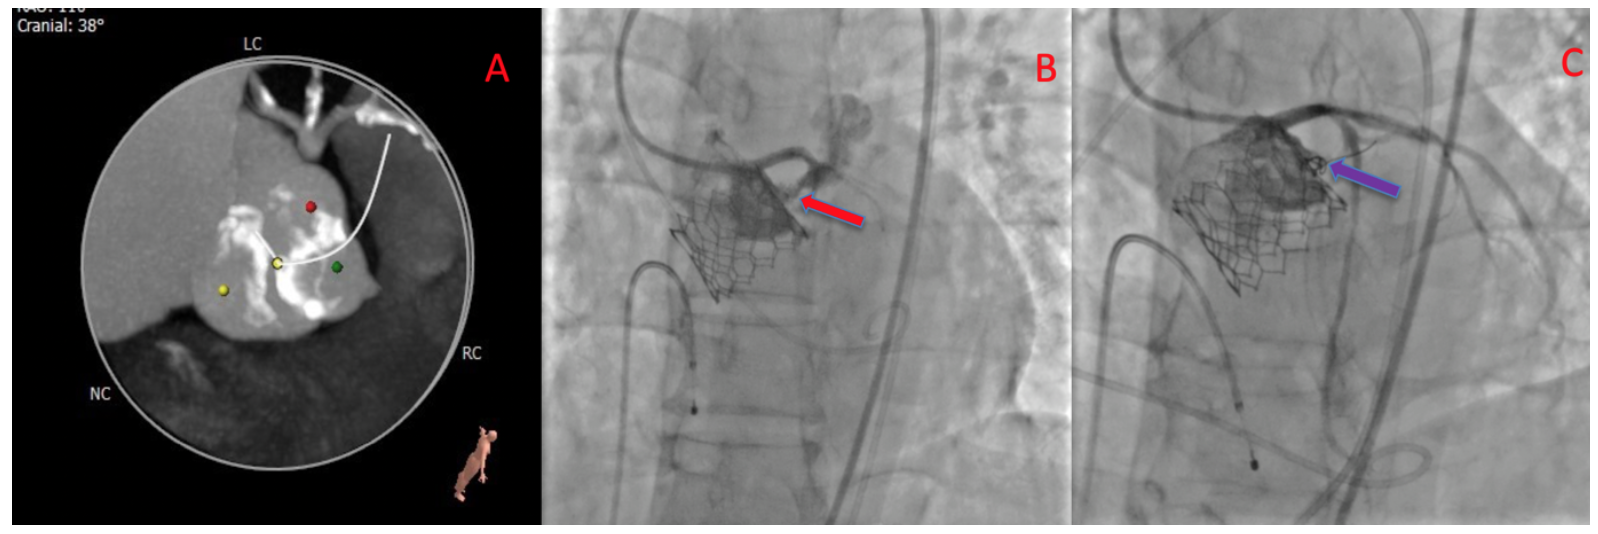

Aortic angiogram of TAVR valve post deployment (red arrow). (A) Safari Tavr Valve Embolization Aortic valve replacement (avr) is the only effective therapy. Embolization of transcatheter aortic valve replacement (tavr) prostheses is a rare and serious procedural complication. Transcatheter valve embolization and migration (tvem) are potential complications of transcatheter aortic valve implantation (tavi) (1). Aortic stenosis (as) is a common valvular heart disease, especially prevalent in the elderly population, and symptomatic severe as. Capture. Tavr Valve Embolization.